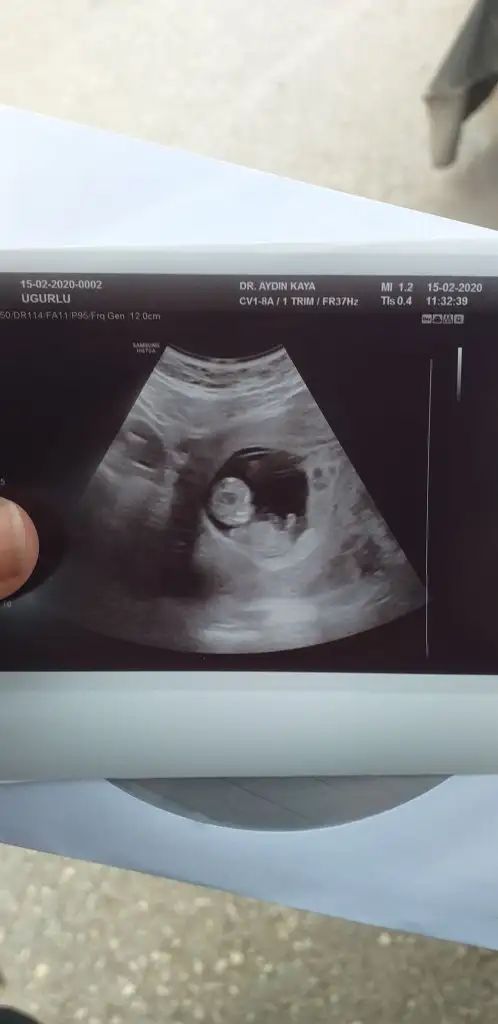

Dün öğrendim sonucu sağlıklı bir kızçe annesi olucakmışım tahminlerin için teşekkürlerUsg kaç haftalık başka usg varsa paylaşın 11 +yada 12+

Merhaba 9 haftalığızSaglıkla gelsin prensesevet tahmimde kız gibiydi